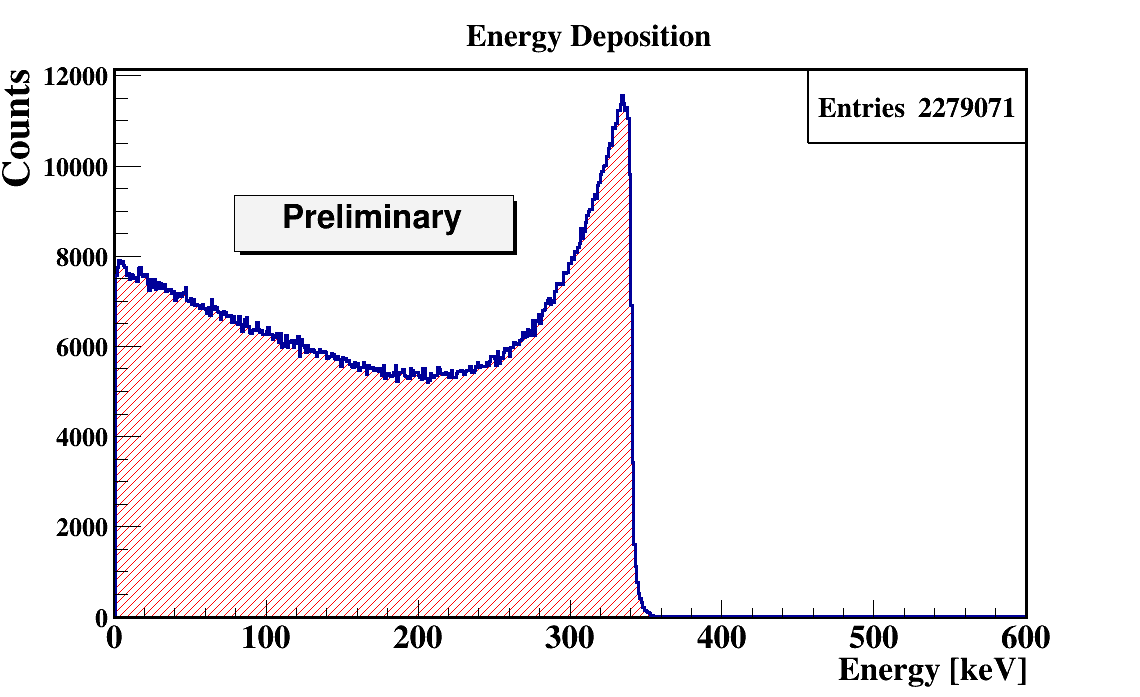

In order to quantify the J-PEM geometry we have performed Monte-Carlo simulations. The simulations were performed using the GATE package. GATE (Geant4 Application for Tomographic Emission) is a Monte Carlo simulation platform developed by the Open-GATE collaboration [40] based on Geant4 software. It is dedicated to numerical simulations in medical imaging and radiotherapy. It utilizes an easy macro mechanism to configure the experimental settings for computed tomography, single photon emission computed tomography, positron emission tomography as well as optical imaging (bioluminescence and fluorescence) or radiotherapy. In the simulations the full geometry of the J-PEM detector and the composition of the detector material were taken into account. The interactions of photons in the scintillators were simulated by GATE. In the simulations we assumed that annihilation source is placed in the center of the detector and that the back-to-back photons (each with energy of 511 keV) from the Ps annihilation are isotropically emitted. Energy deposition inside the plastic scintillator is shown in Fig.7. According to the performed simulation we are able to register 4.33% of generated back to back events. After adding the condition that both photons deposited at least 200 keV energy fraction of register annihilation drop to 0.8 % . Such a condition is needed for the suppression of the scatter fraction [41]. We found that there was 11.3% primary back-to-back registered events where at least one photon scattered in WLS.